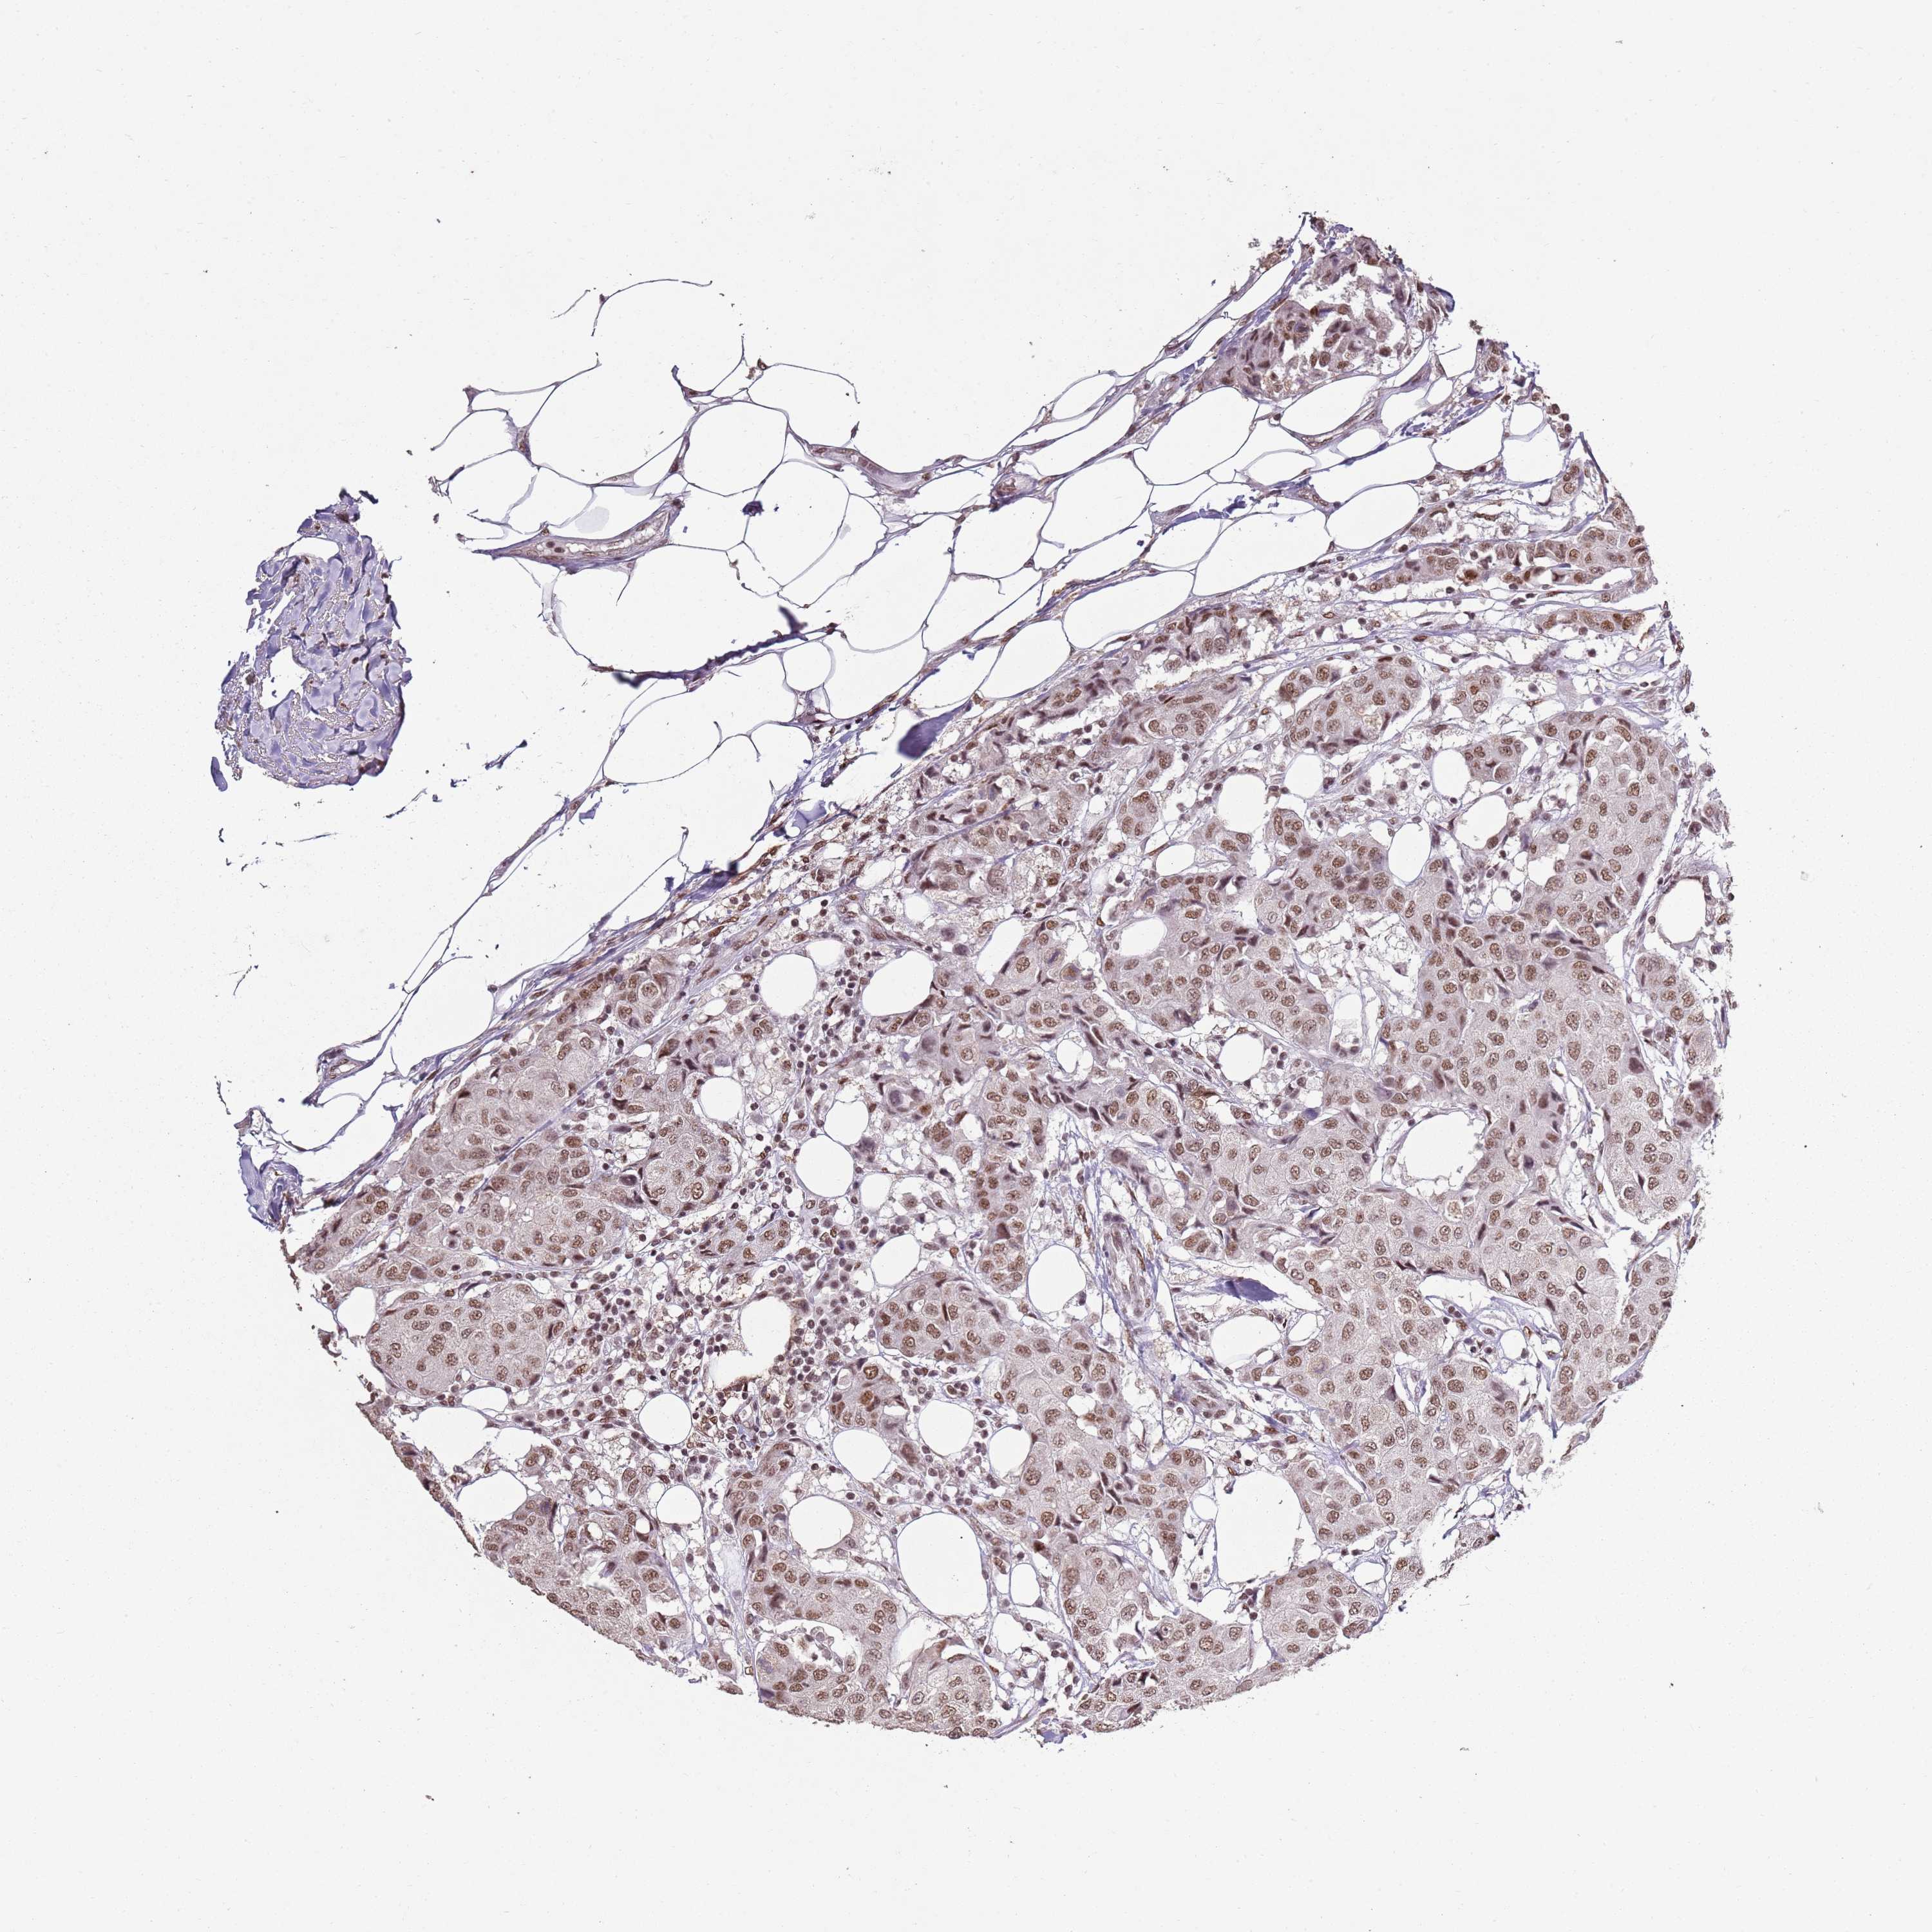

CANCER BREAST CANCER Show tissue menu

BRCA TCGA BRCA VALIDATION PROTEIN EXPRESSION